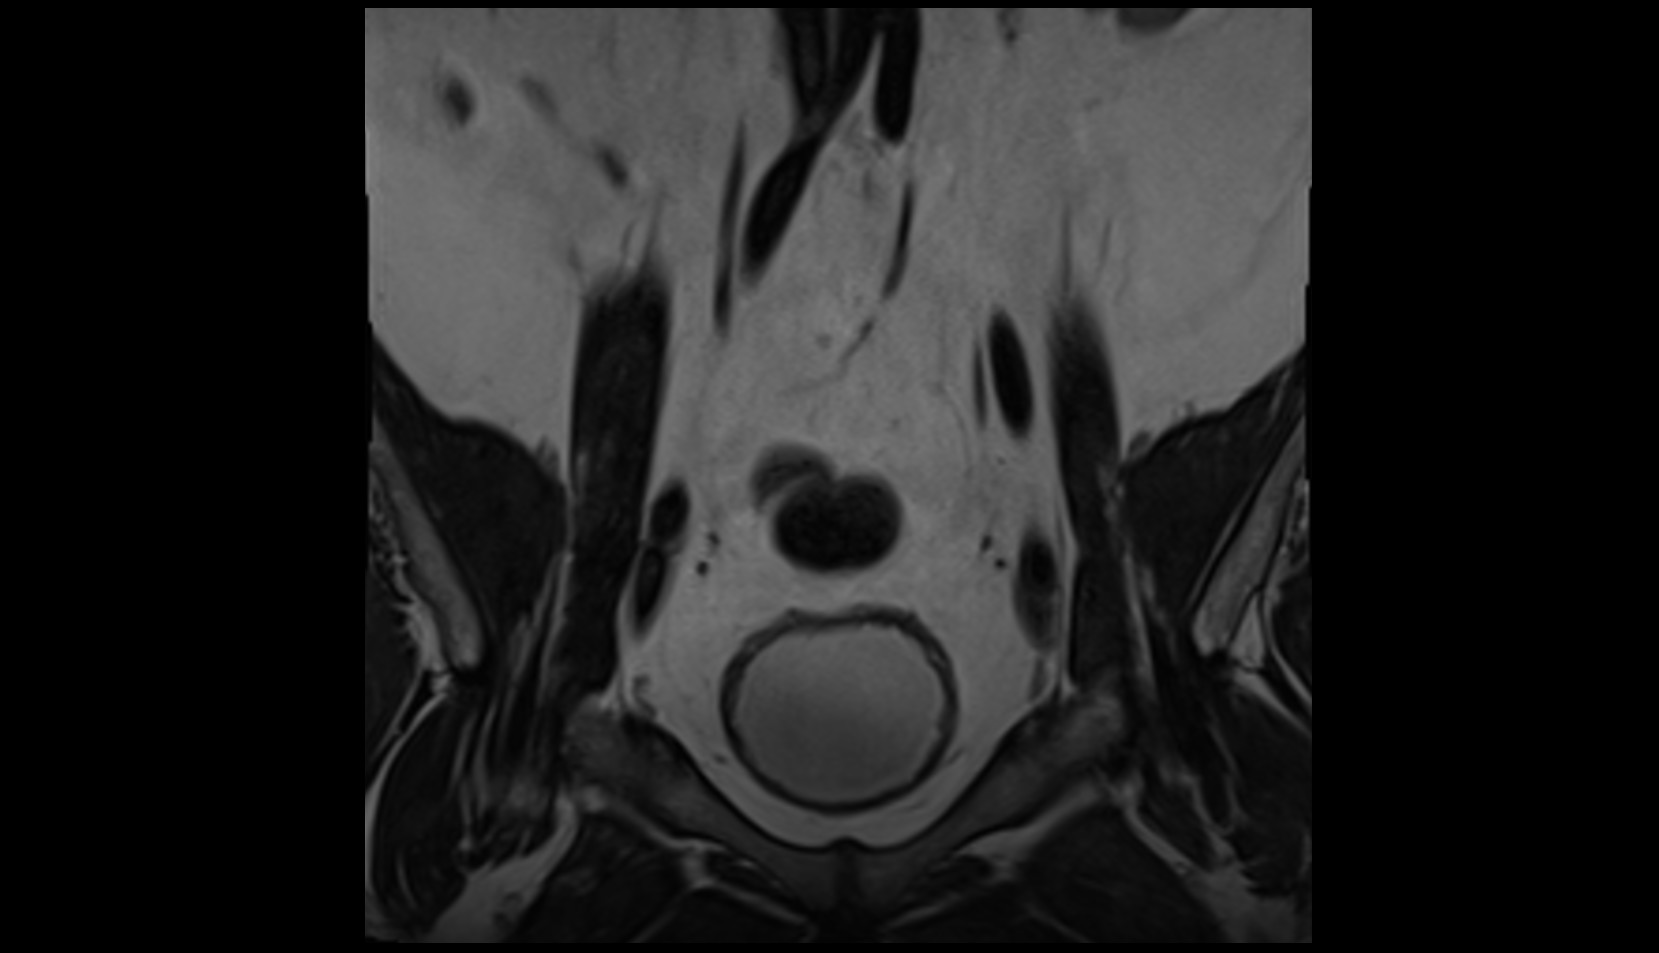

- Peripheral zone of prostate

- Anterior Fibromuscular Stroma of prostate

- Central zone of prostate

- Transitional zone of prostate